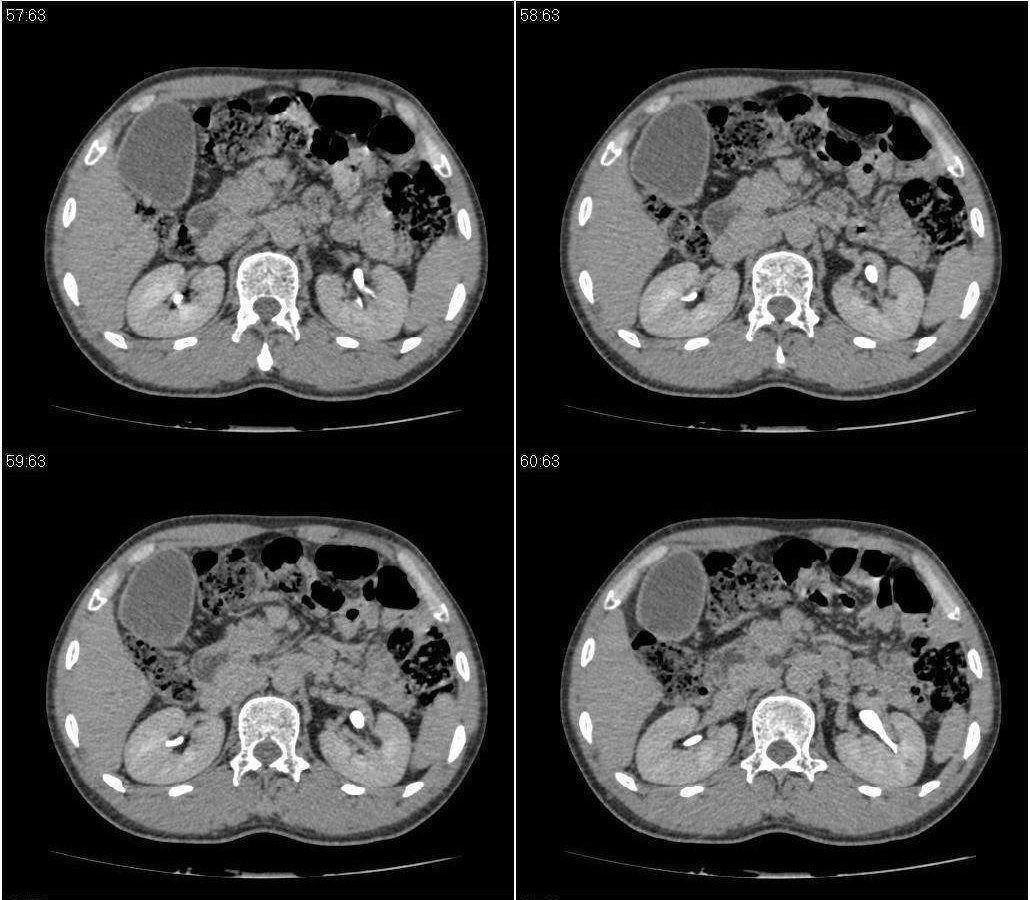

标题: CT21384:男性,50岁。发现无痛性黄疸十余天,B朝提示肝胆管 [打印本页]

标题: CT21384:男性,50岁。发现无痛性黄疸十余天,B朝提示肝胆管

1.考虑:壶腹占位病变(癌?)。

2.胆系低位梗阻:肝内外胆管扩张,胆囊增大,胰管扩张。

胆系低位梗阻:肝内外胆管扩张,胆囊增大,胰管扩.壶腹癌。

胆系低位梗阻(肝内外胆管扩张,胆囊增大,胰管扩张);考虑胰头癌或壶腹癌所致。

胆系低位梗阻(肝内外胆管扩张,胆囊增大,胰管扩张,钩突似有占位);考虑胰头癌